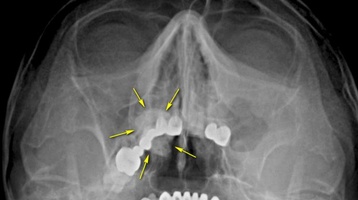

Що таке поліпи в носі

Поліпи в носі – це патологічний процес, який розвивається в разі хронічного запалення слизової, викликаного алергією або інфекцією.